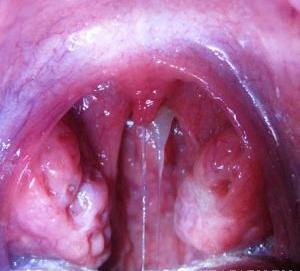

Симптомы аденоидов, увеличенные глоточные миндалины